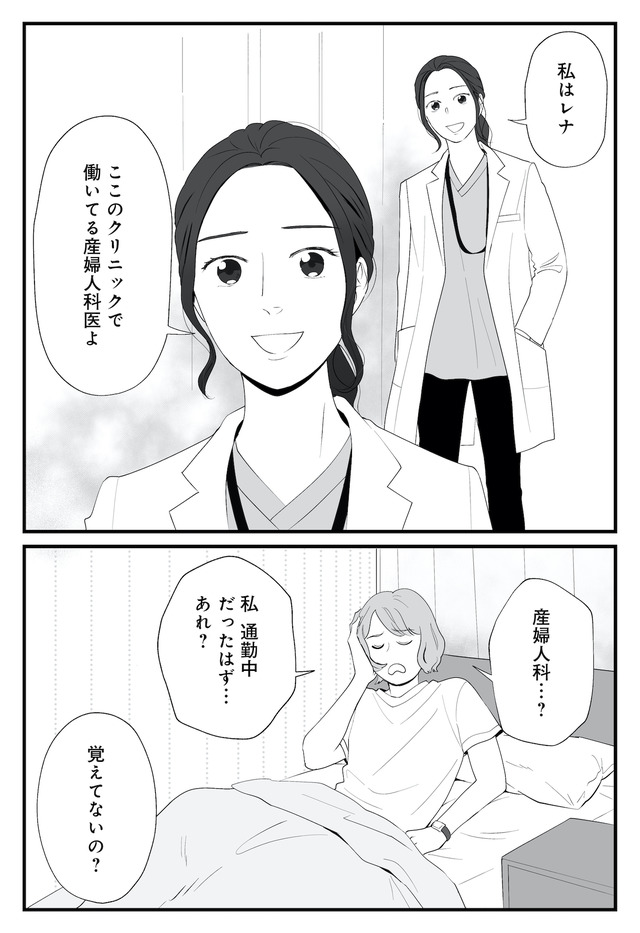

生理痛やPMSに苦しむあかり。通勤中、貧血で倒れて病院に運ばれたことをきっかけに、自分にあった生理用品や治療法を教えてもらうことに。

※本記事は、漫画・くゑ 、監修・高橋 怜奈 の書籍『産婦人科医に聞く わたしとカラダの選択肢』から一部抜粋・編集しました。